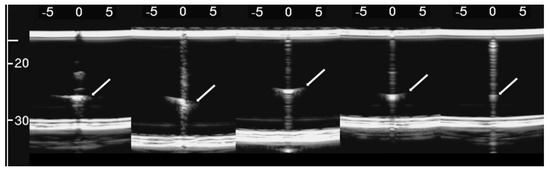

Figure 5 shows the two ultrasound vertical artifacts with different zoom degrees, which were obtained on the models that are illustrated in the left image of Figure 1. The seven air cylinders provide two different types of artifacts (a1 and a2) which are indicated in Figure 5. The pair of short artifacts a1 is provided by multiple reflections between the two air cylinders which limit the aperture of the trap. In fact, a distance of about 1 mm between two replicas of their repetitive patterns can be derived from Figure 5 according to the assumed propagation speed of 1500 m/s. The longer artifact a2 is generated by the re-radiation of the acoustic energy which has been transmitted to the trap and starts when the beam is reflected from the bottom of the trap. The artifact generated by the agar cylinder has a repetitive pattern that is not seen in the artifact generated by the seven air cylinders and seems to be related to the diameter of the trap. In fact, a distance of about 5 mm between two replicas of the repetitive pattern can be derived from Figure 5 according to the assumed propagation speed of 1500 m/s. This simple example shows how different artifacts can be obtained from acoustic traps with similar volumes and similar shapes. This example also shows how long artifacts can be obtained when an interstitial volume, surrounded by aerated spaces, is linked to the pleura plane by means of a small (as compared to the interstitial volume) channel.

Figure 5. Two ultrasound vertical artifacts with different zoom degrees, which were obtained on the models illustrated in the left image of Figure 1, are shown. The pair of short artifacts a1 is provided by multiple reflections between the two air cylinders which limit the aperture of the trap. The longer artifact a2 is generated by the re-radiation of the acoustic energy and starts when the beam is reflected from the bottom of the trap.